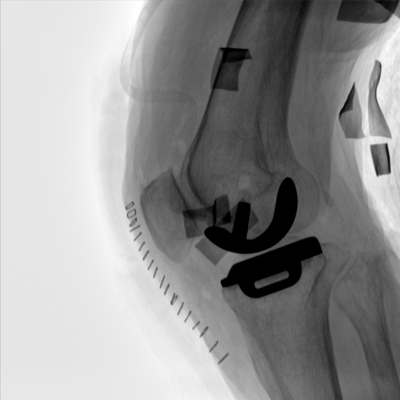

大尺寸動態(tài)平板探測器,高DQE、低噪聲、圖像清晰。采用多分辨率圖像增強(qiáng)處理技術(shù),不同部位不同圖像處理算法,滿足客戶多樣化的需求。

采用智能變頻脈沖透視技術(shù),優(yōu)化圖像質(zhì)量的同時降低輻射劑量,呵護(hù)醫(yī)患健康